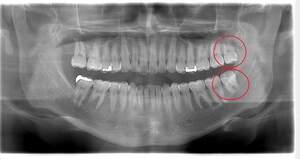

親知らずが虫歯になっている症例

- 抜歯前写真(レントゲン)

| 年齢 | 30代・女性 |

|---|---|

| 主訴 | 親知らずが虫歯になっている |

| 親知らずの生え方 | 半分埋まっている、横に生えている |

| 抜歯時間 | 45分 |

| 費用 | 約8,000円(CT代含む) |

| 抜歯内容 | 当院に通院中の患者様です。 当日は痛みがあったため抗生剤と鎮痛剤にて炎症を抑え、後日歯ぐきを切開し、抜歯を行いました。 下顎の両方とも横向き生えていて、手前の歯も虫歯になっているため抜歯をすることになりました。 麻酔を行い親知らずの奥に切開を入れて、歯を覆っている周りの骨を削りました。 その後歯の頭を削って出して、残った根の部分に器具を引っかけて根の部分を取り出しました。切開した歯ぐきは糸で縫ったため約1週間後に糸取りをして終了となりました。 この症例では、横向きに生えている歯の根の先端が神経に近い場所にあったため、術後のリスクとして知覚の麻痺が出てしまう可能性がありましたが、事前にCTを撮影し、歯の位置、根の方向、神経との位置関係を確認していたため、術後の麻痺など出ることなく経過は良好です。 |